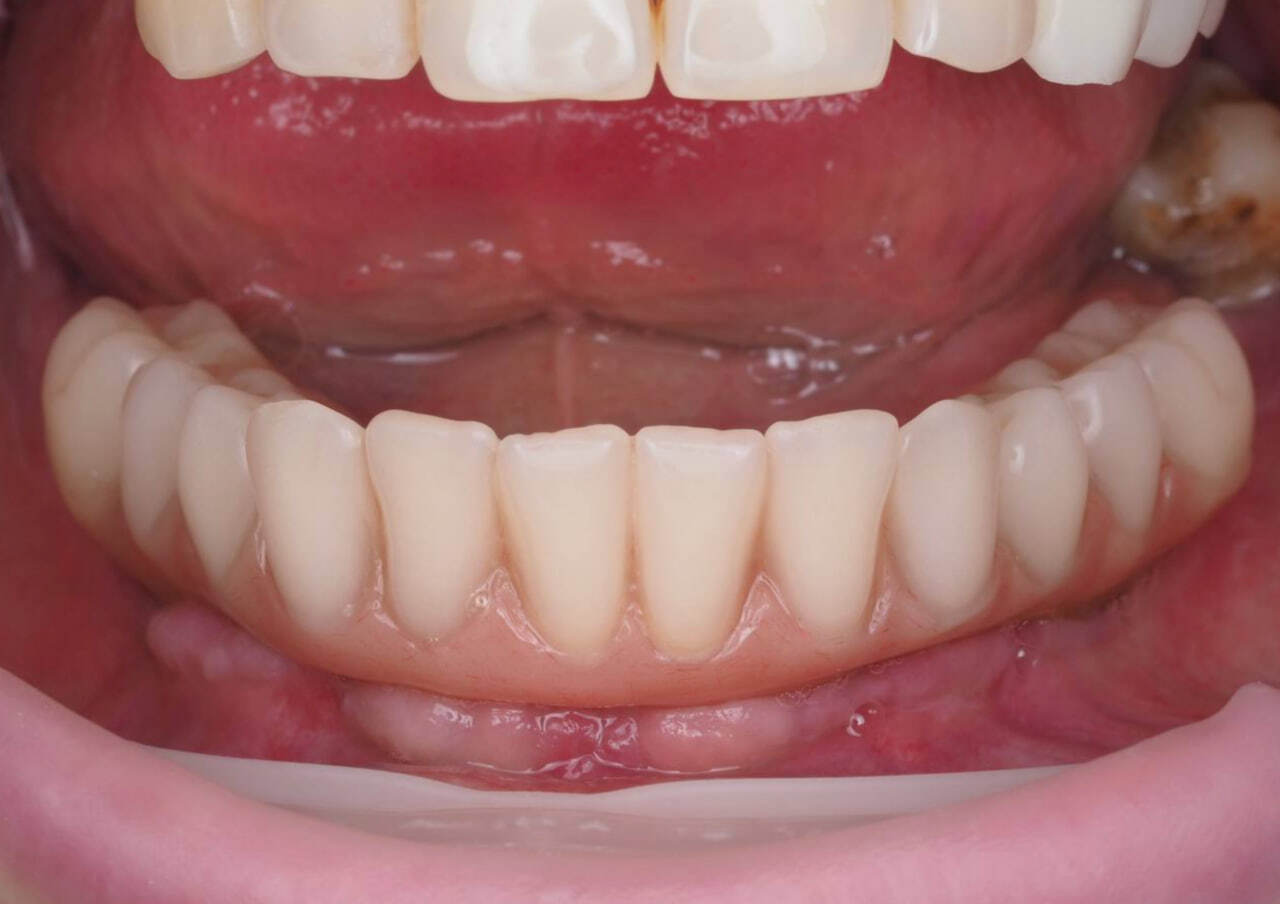

После снятия адаптационного временного протеза прекрасное состояние мягких тканей.

Рентген-контроль полной работы.